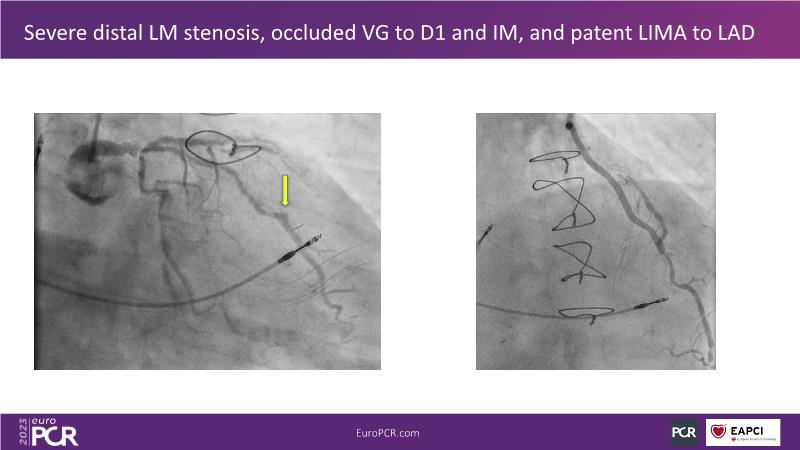

The aim of this session is to address the question of how to optimise outcomes for high-risk patients by analyzing two real-life cases for discussion: a distal calcified left main trifurcation and a high-risk PCI with orbital atherectomy.